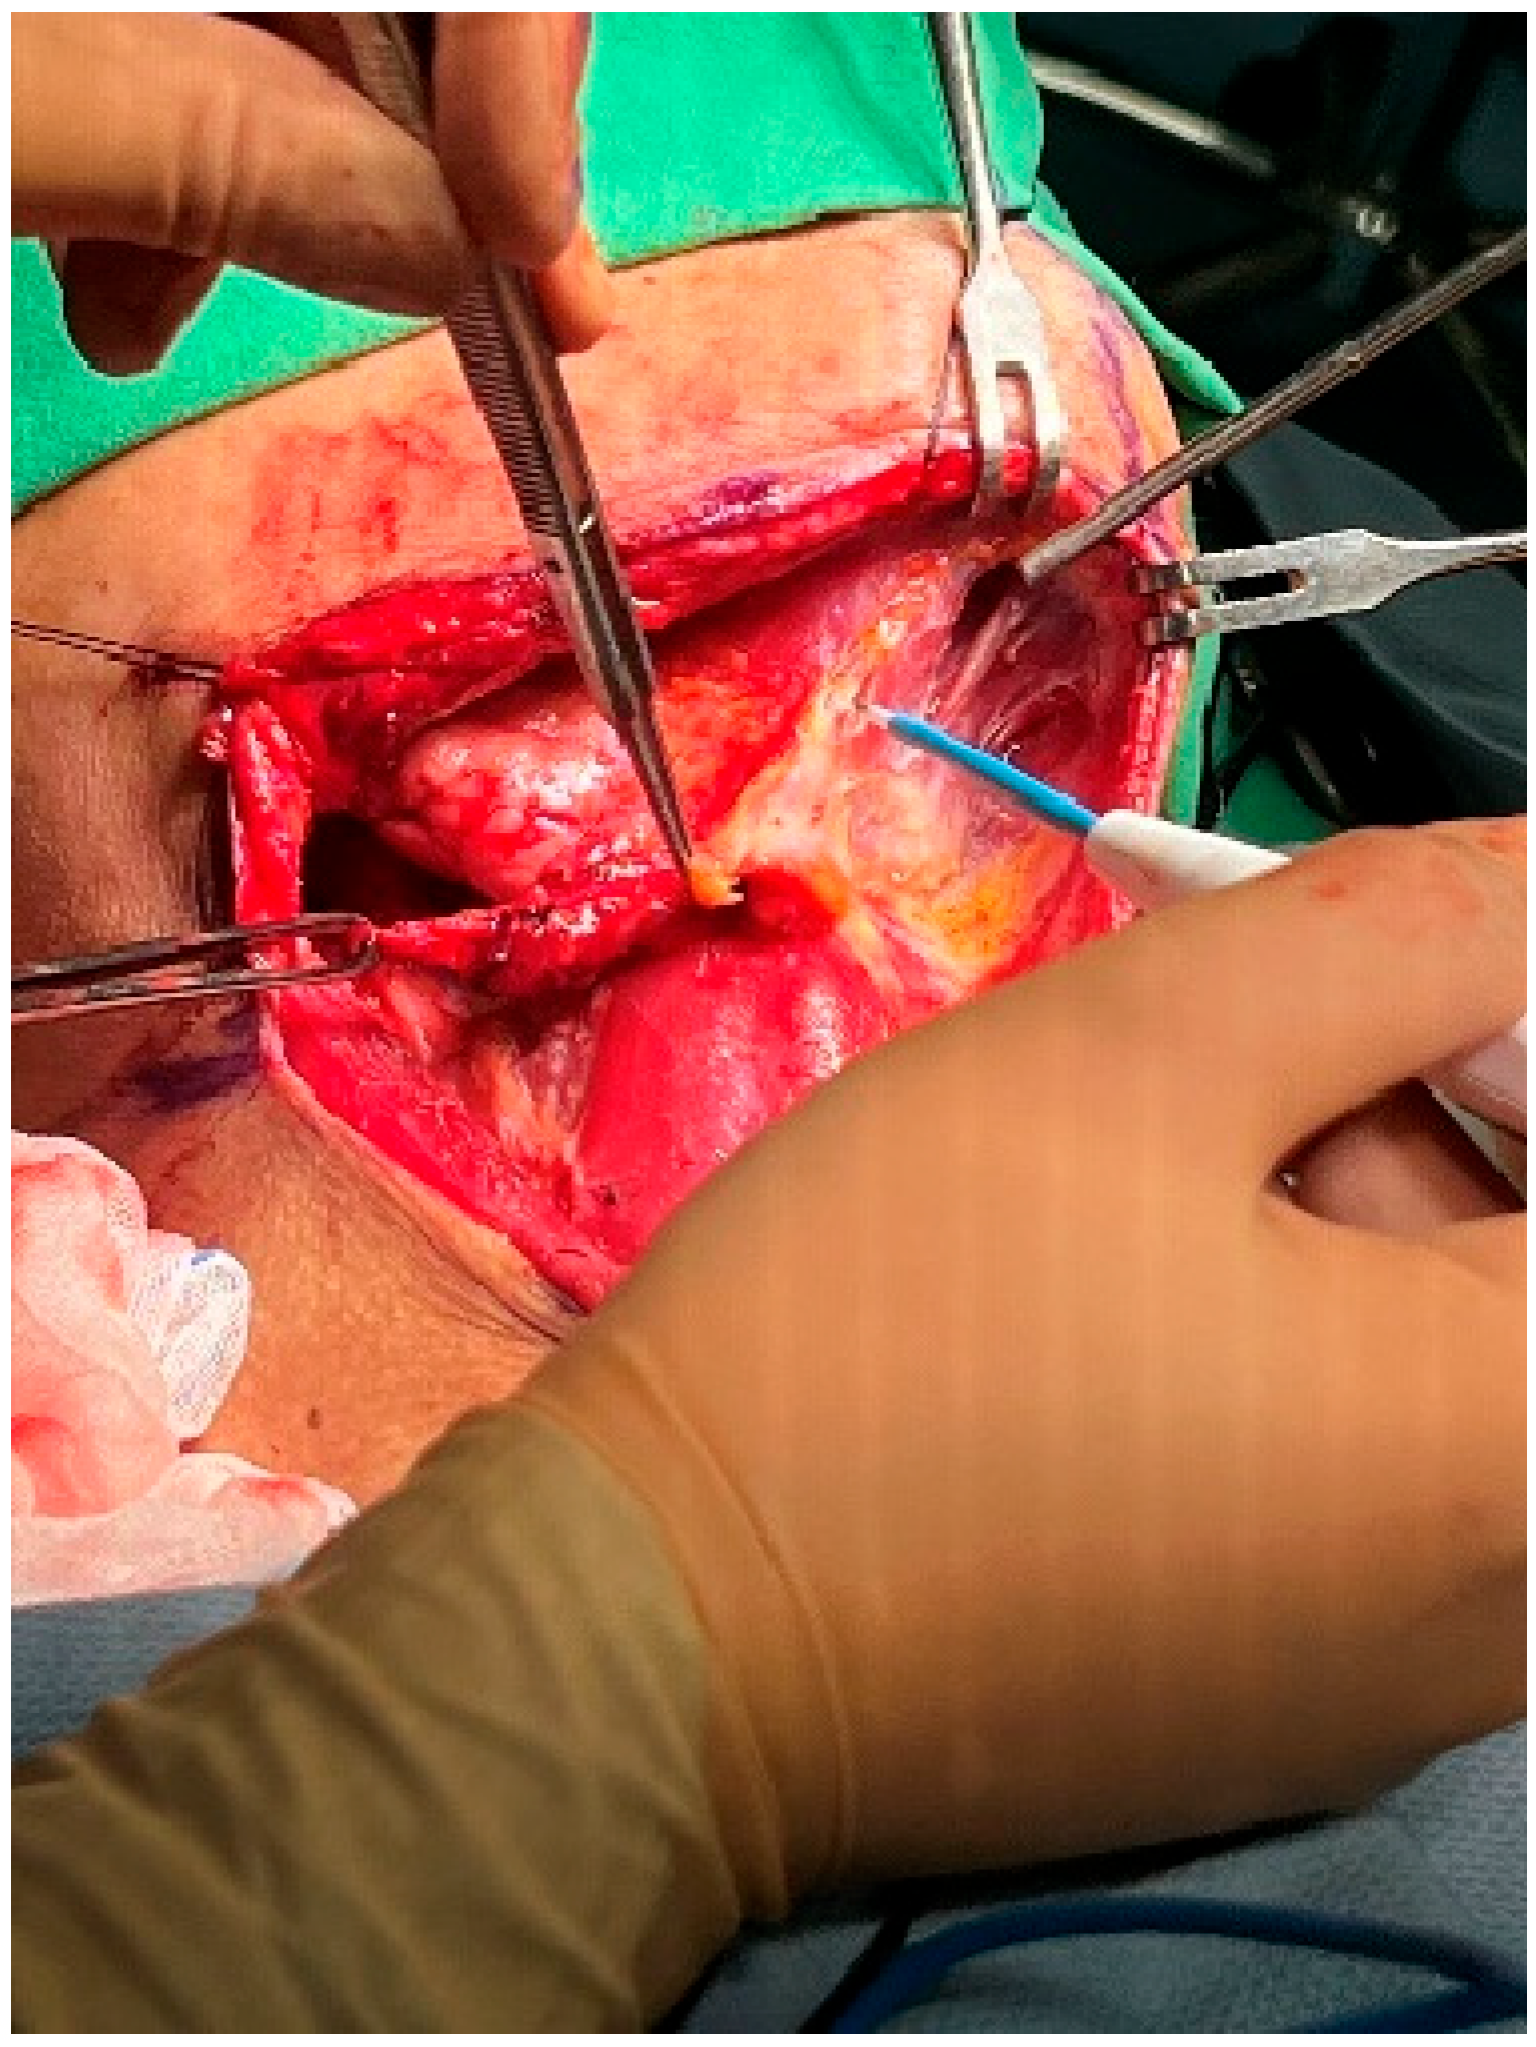

At this point, the neck dissection was complete, and the facial artery was identified, which helped differentiate between the internal and external carotid arteries. By opening the carotid sheath using curved pean forceps, the common carotid artery was made visible. Tracing upward led to the bifurcation of the carotid artery. The presence of branches serves as a characteristic feature of the external carotid artery. The superior thyroid artery, the first branch of the external carotid artery, originates below the level of the greater horn of the hyoid bone. The lingual artery, closely associated with the hyoid bone, originates from the external carotid artery above the level of the greater horn [28]. The root of the facial artery is located obliquely beneath the digastric and stylohyoid muscles [29,30]. These branches were used to identify the external carotid artery. After separating the external carotid artery from the internal carotid artery and vagus nerve, a Rummel tourniquet was used to restrict the external carotid artery and control bleeding (Figure 10).

Figure 10.

Rummel tourniquet restriction of the left ECA.